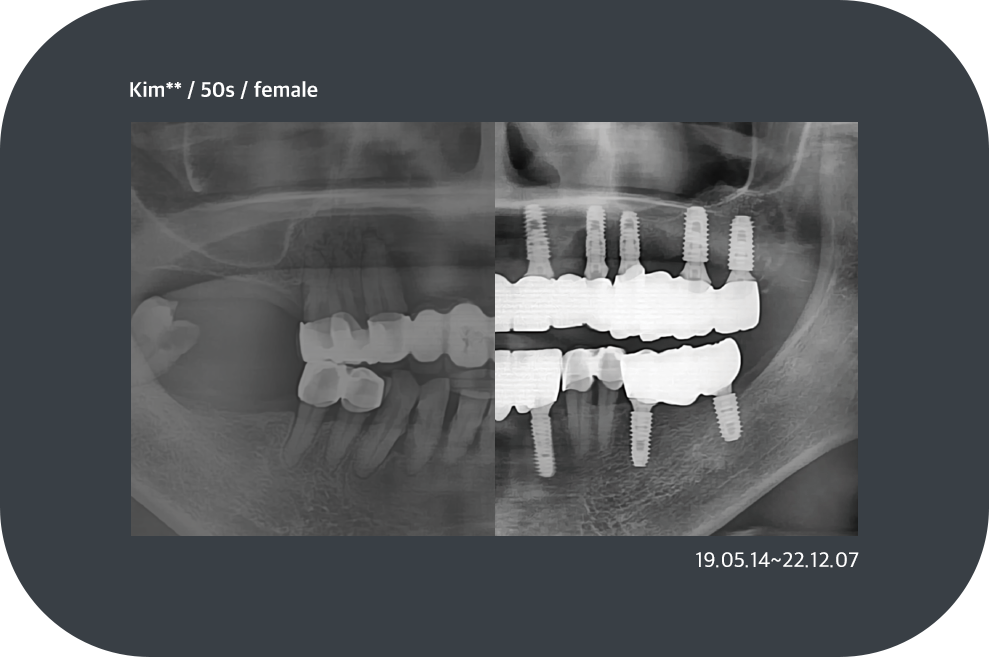

치료사례

임플란트 치료사례

implant_case01

implant_case02

implant_case03

implant_case04

*모든 증례 사진은 의료법 제23조, 제56조에 의거하여, 당사자의 동의하에 게시하였습니다.

*치료 사진은 모두 본원에서 치료한 환자분의 사진입니다.

*치료 사진은 모두 동일인의 사진이며, 동일조건에서 촬영하였습니다.

*개인의 차이에 따라 시술 및 수술 후 부작용이 발생할 수 있으며, 의료진과 충분한 상담을 받으시기 바랍니다.